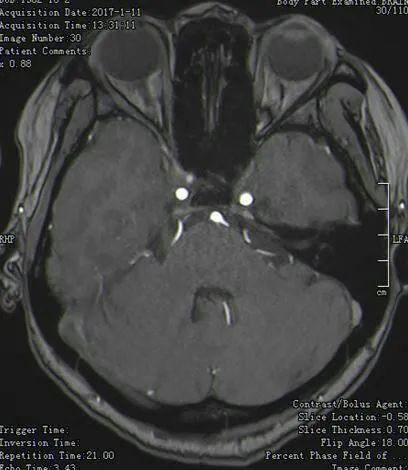

第二例 面肌痉挛何某,女,36岁,“左面部不自主抽动2年,加重3个月”入院

左侧面神经与小脑前下动脉与小脑后下动脉关系紧密

注意了,这是两根不同的血管

血管穿过面听神经之间

术中暴露小脑前下动脉和小脑后下动脉

剥开听神经可见细长面神经,小脑前下从面听神经之间穿出,并与小脑后下动脉被蛛网膜包裹形成系带

细长面神经可见系带形成的压迹

TEFLON棉垫开两根责任血管术后患者再无挤眉弄眼的表现